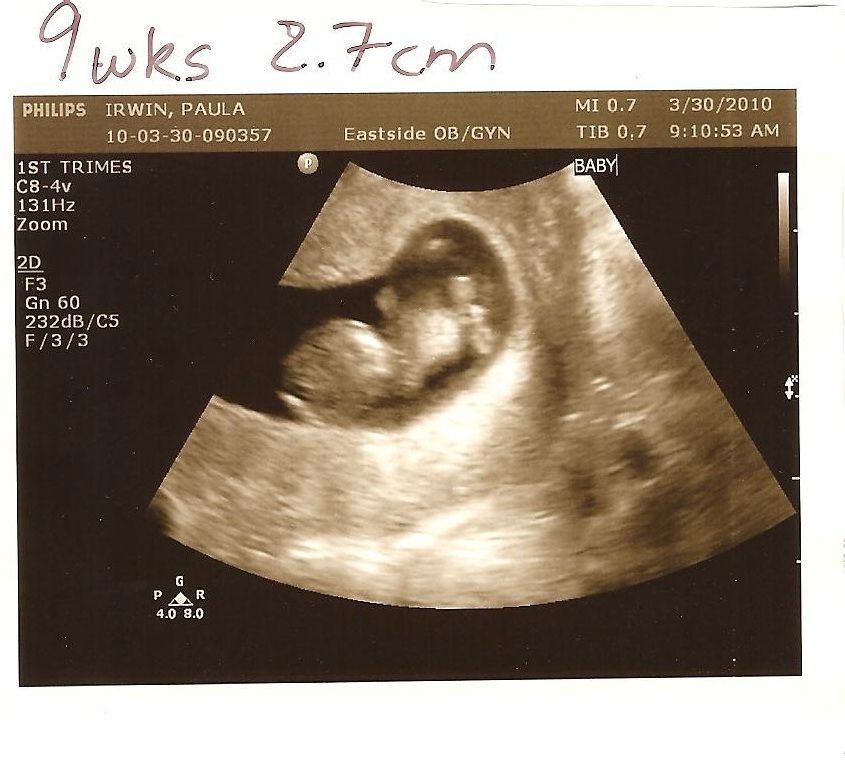

Irwin with an “I”: 9 Week Ultrasound